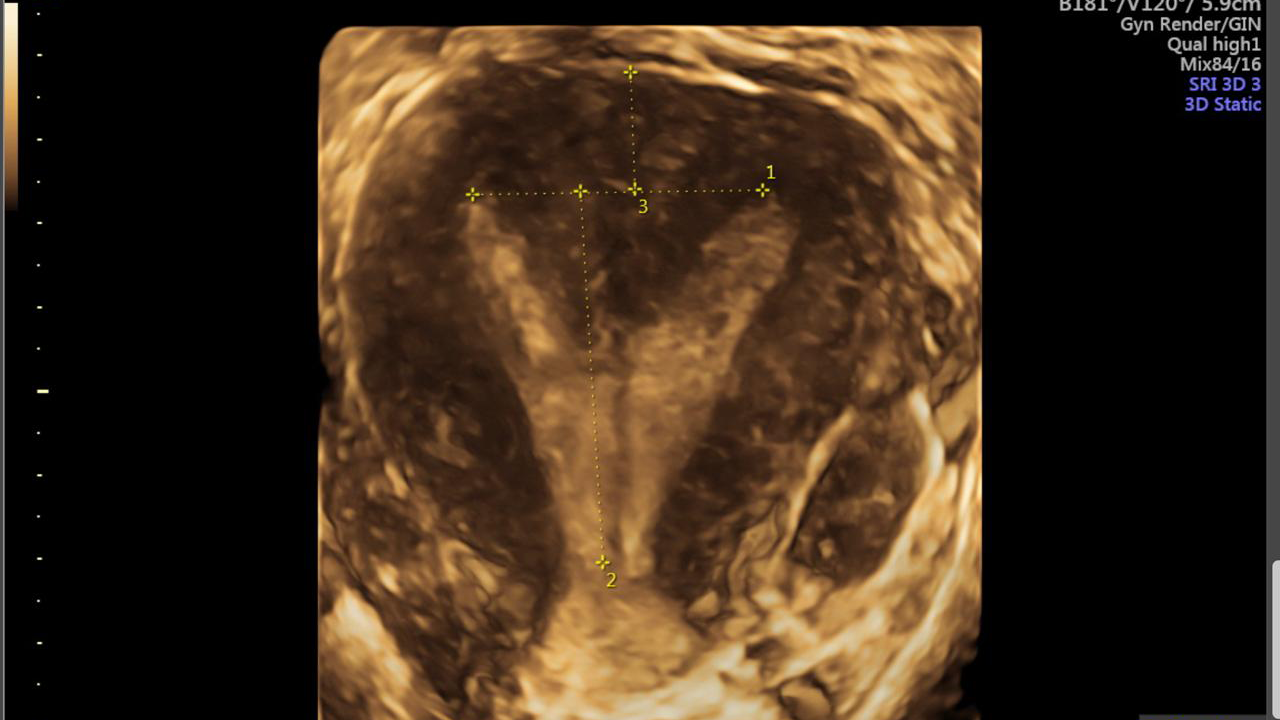

Ecografía transvaginal

Útero septado: el útero tiene una pared divisoria en su interior.

Útero bicorne: el útero tiene forma de corazón, parcialmente dividido.